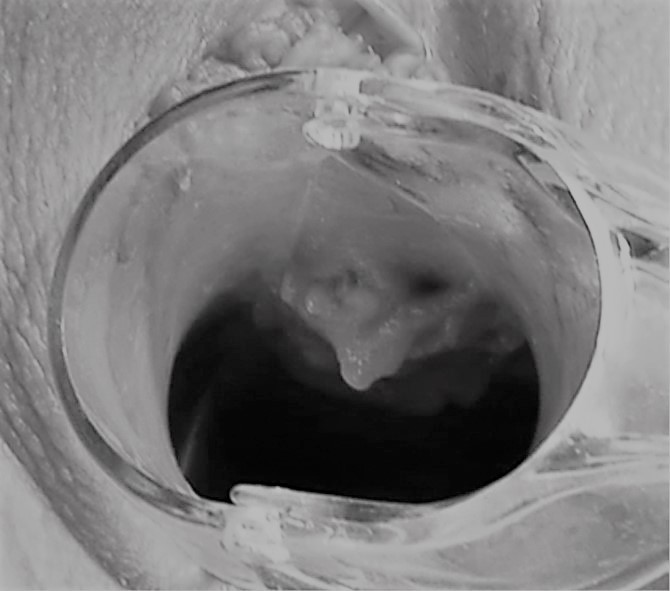

Ход операции

Врач вводит гиалуроновую кислоту непосредственно в точку G, которую предварительно определяет при пальпации, тем самым увеличивая ее упругость и амортизацию.